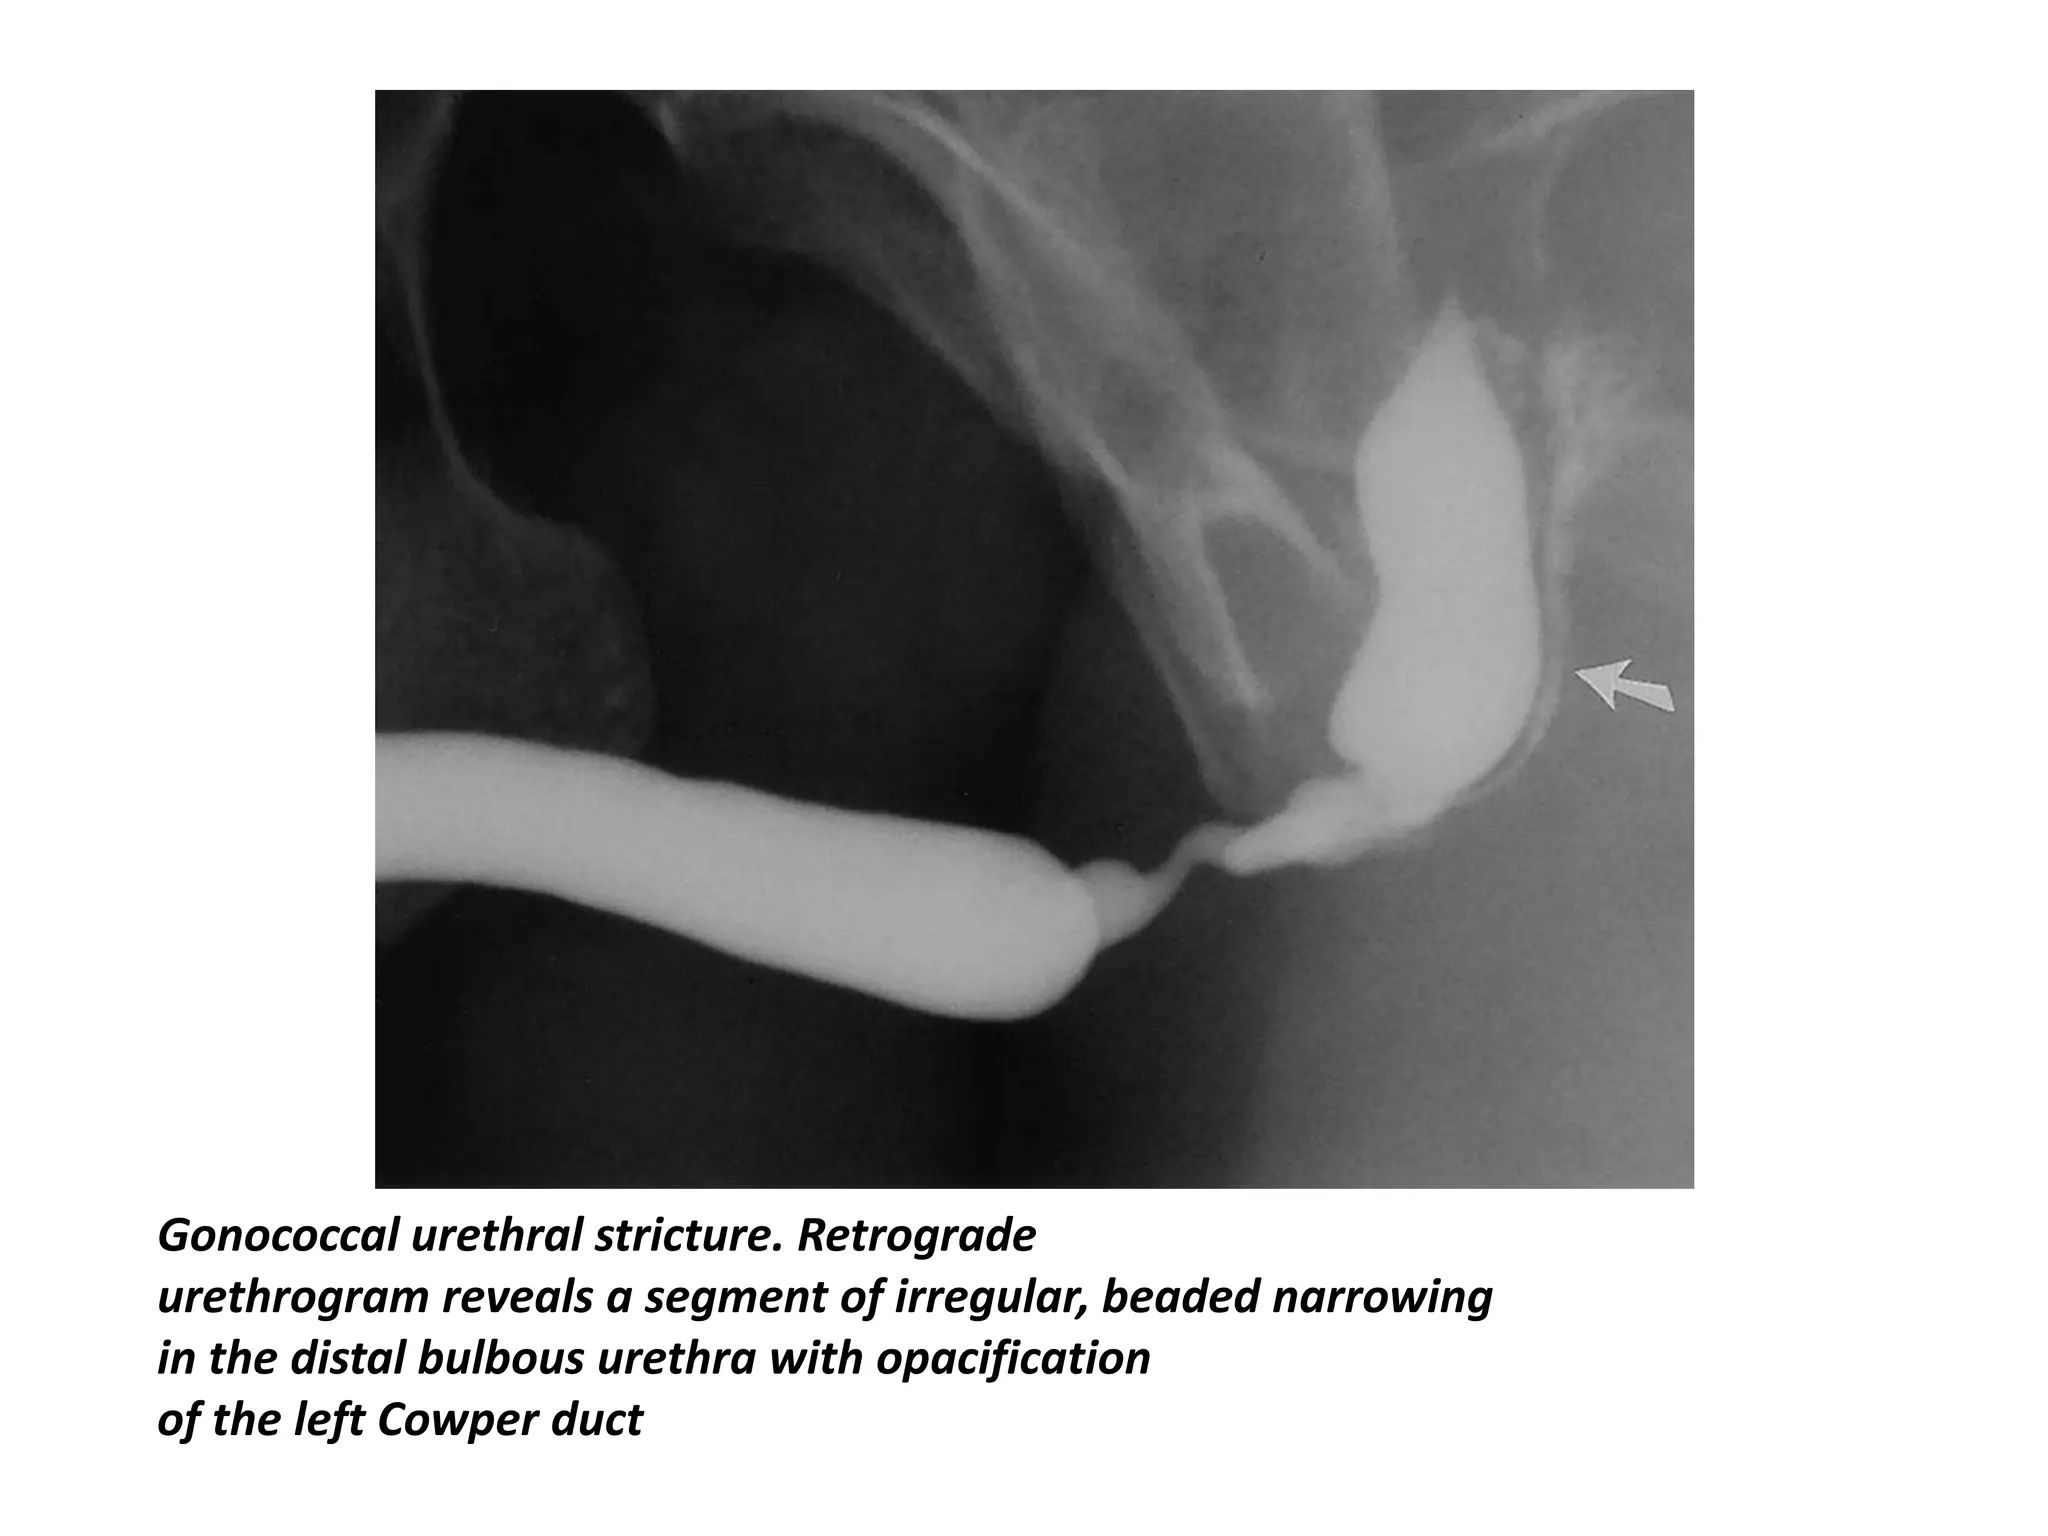

• The typical urethrographic finding in gonococcal urethral stricture is

an irregular urethral narrowing several centimeters long.

• While the bulbar urethra is the most common area of occurrence,

gonorrheal strictures may occur anywhere in the anterior urethra or

may even involve the entire anterior urethra

Gonococcal urethral stricture. Retrograde

urethrogram reveals a segment of irregular, beaded narrowing

in the distal bulbous urethra with opacification

of the left Cowper duct